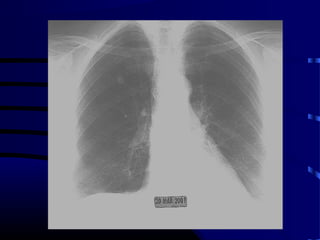

Question • A 60year old white male smoker without symptoms presents for a routine annual physical and a CXR is performed. What test do you order next?

• 79.

Question • A) CTchest with IV contrast. • B) CT-guided transthoracic needle biopsy. • C) Review prior chest X-rays. • D) Full body PET scan. • E) Surgical resection.

• 80.

Answer • A) CTchest with IV contrast. • B) CT-guided transthoracic needle biopsy. • C) Review prior chest X-rays. • D) Full body PET scan. • E) Surgical resection.